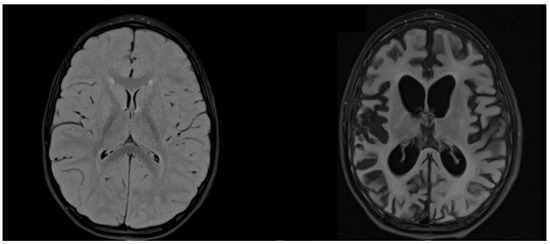

| A | 5-day escalation regimen *:one dose of 1,000,000 U/m2 weekly for 6 months; 1,000,000 U/m2 every 2 weeks for 6 months Total: 1 year  | Oral inosiplex 100 mg/kg/day Total: 2.5 years  | Antiepileptic drugs and motor rehabilitation  | 2B | Slow brain electrical activity, with a plurifocal peak and irregular short periods of voltage suppression | Progressive cortical atrophy, significant reduction in the corpus callosum | 2.8 years later | 2C from 2A; slow progression  | Spastic tetraparesis, absent language, good understanding | Left-sided depressed activity without an ictal or periodic pattern |

| B | 5-day escalation regimen *: one dose of 1,000,000 U/m2 weekly for 6 months; 250,000 U/day through a continuous intrathecal infusion pump for 2.5 years Total: 3 years  | Oral inosiplex 100 mg/kg/day Total: 3.6 years  | Antiepileptic drugs and motor rehabilitation  | 2C | Unorganised cerebral electrical activity and paroxysms of large slow waves at 2 c/s, with a periodic course and diffuse EEG expression | NA | 4 years later | 2C from 2C; stabilisation  | Cognitive impairment, walking with support, ability to express primary needs | Poorly organised electrical activity without pathological potentials |

| C | 5-day escalation regimen *: one dose of 1,000,000 U/m2 weekly for 12 months; 1,000,000 U/m2 monthly for 2 years Total: 3 years  | Oral inosiplex 100 mg/kg/day Total: 3.2 years  | Antiepileptic drugs and motor rehabilitation  | 3 | Sequences of 2 c/s delta potentials with epileptiform elements in frontal–central regions bilaterally; no periodic pattern | Progressive atrophy, significant reduction in the corpus callosum, increased dilation of the ventricular system | 7 years later | 2D from 3; improvement  | Spastic tetraparesis, improved environmental participation, oral feeding | Poorly organised electrical activity with ictal episodes associated with acoustic stimulation |

| D | 5-day escalation regimen *: one dose of 1,000,000 U/m2 weekly for 3 months; after 3 months without therapy, the same therapy regimen repeated for another 6 months Total: 9 months  | Oral ribavirin 20 mg/kg/day in two doses for 7 days; one dose of IgEV (1 g/kg) vitamin A 50.000 UI 2 times a day for 1 month  | Antiepileptic drugs and motor rehabilitation  | 2B ** Progression  | Slow cerebral activity with high-voltage theta waves (5 Hz) in centrum-temporo-parietal regions | Frontal right-sided cavitation area, resulting from the previous abscess; rapidly progressive global atrophy with extension of leukodystrophy; no recent tissue lesions | 1 year later | 2D from 2A; progression  | Spastic tetraparesis, dystonia and tremors, enteral feeding | Poorly organised and asymmetrical electrical activity without an ictal pattern  |